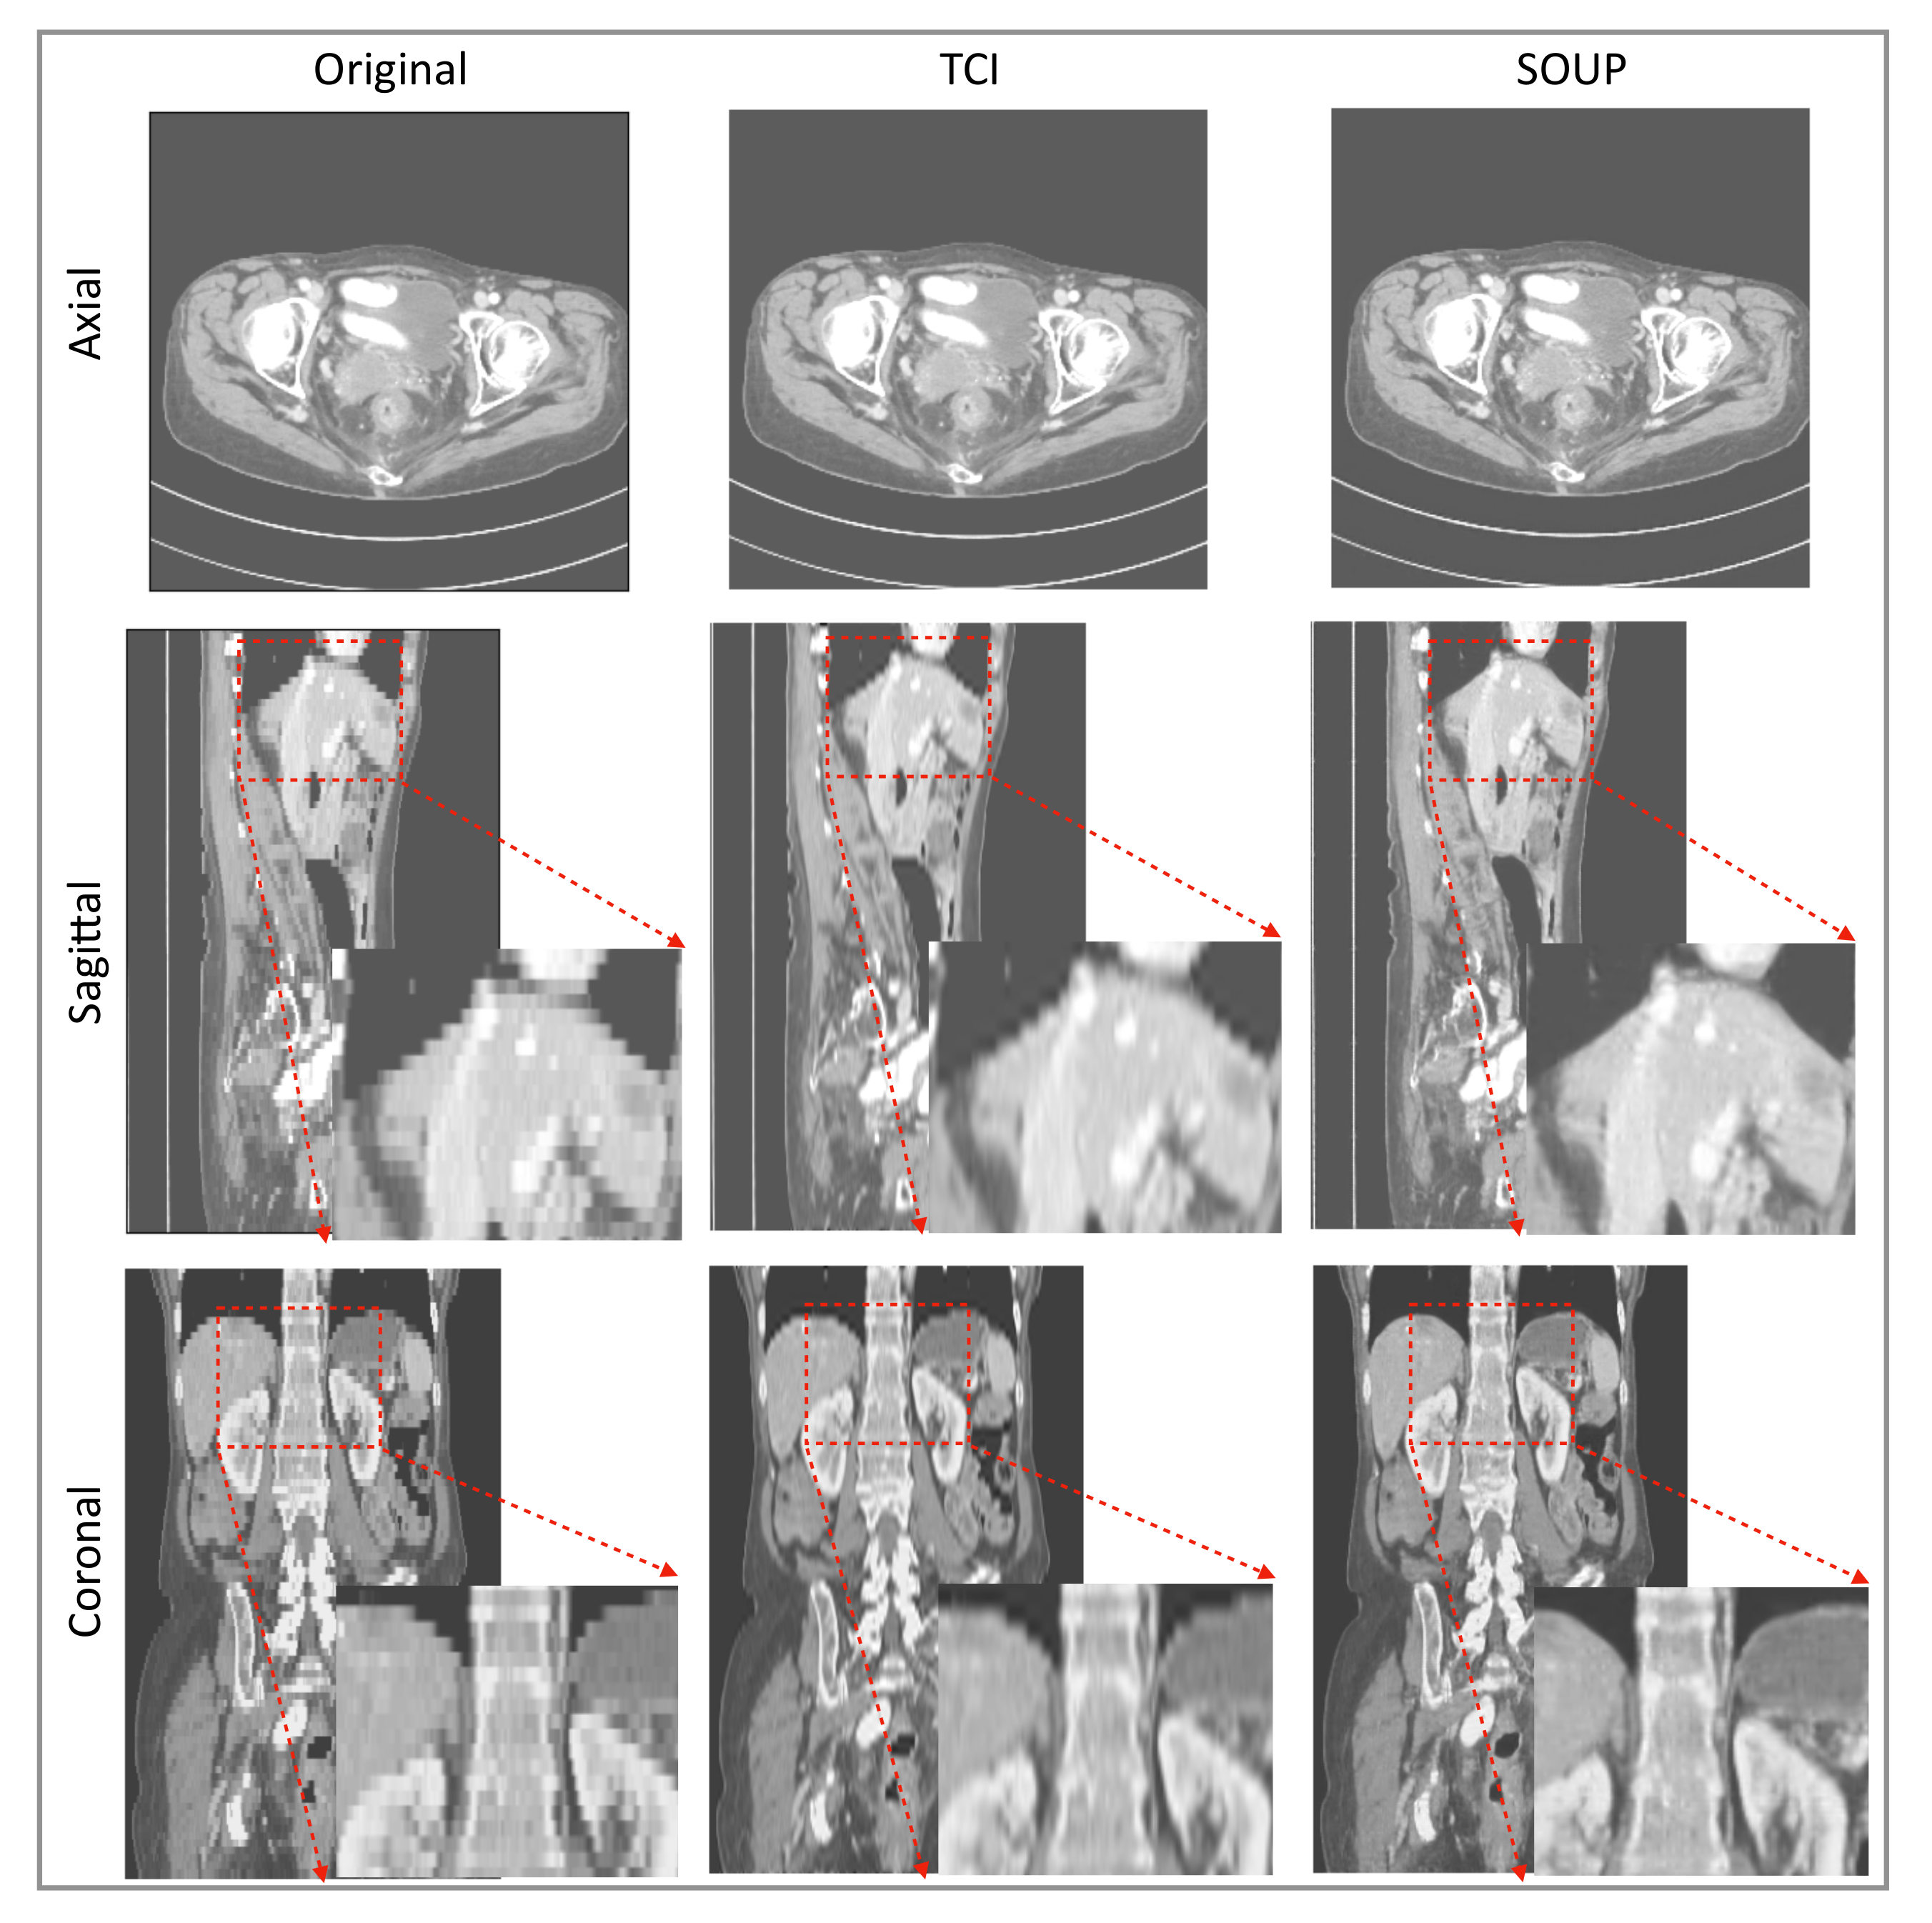

3.4. Generalization to Other Medical Imaging Modalities, e.g., CT

We also apply our scale-attention SR model to CT data. Figure 6 and Figure 7 show the SR-interpolated (SOUP) and conventionally interpolated images on abdominal and pelvic CTs. It is clear from both examples that the SR-interpolated results achieve significantly higher quality than the conventionally interpolated ones in regard to the edges, textual details, and blurring. Those comparisons demonstrate that our scale-attention SR model (SOUP) is a widely generalizable tool for different sampling factors and various applied imaging modalities, which paves the way for more advanced medical image interpolation through deep-learning SR.

Figure 6.

Example of SR interpolation on CT with a sampling factor equal to 4.8. Edges and textual details are better resolved by SR. Blurring is reduced. TCI: tricubic interpolation.